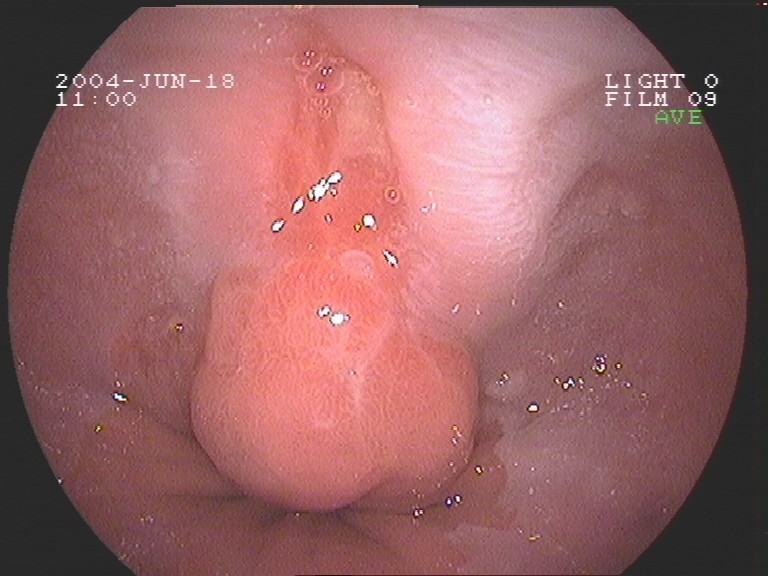

Coloskopie - langgestielter Dickdarmpolyp (Adenom)